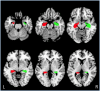

Physical activity facilitates neurogenesis of dentate cells in the rodent hippocampus, a brain region critical for memory formation and spatial representation. Recent findings in humans also suggest that aerobic exercise can lead to increased hippocampal volume and enhanced cognitive functioning in children and elderly adults. However, the association between physical activity and hippocampal volume during the period from early adulthood through middle age has not been effectively explored. Here, we correlated the number of minutes of self-reported exercise per week with gray matter volume of the hippocampus using voxel-based morphometry (VBM) in 61 healthy adults ranging from 18 to 45 years of age. After controlling for age, gender, and total brain volume, total minutes of weekly exercise correlated significantly with volume of the right hippocampus. Findings highlight the relationship between regular physical exercise and brain structure during early to middle adulthood.